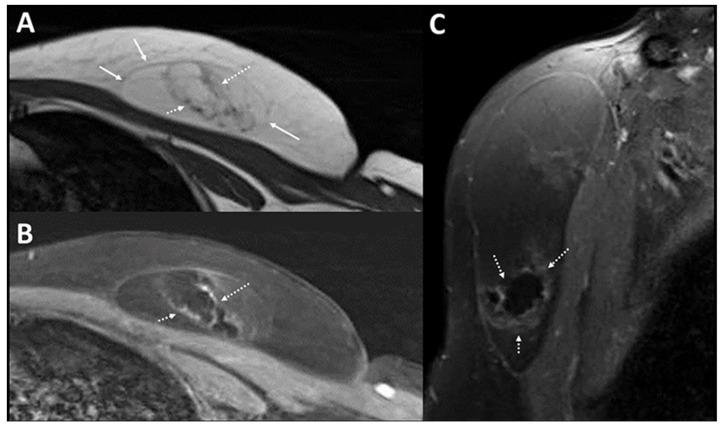

A 50-year-old woman with no past medical history presented with a left anterior chest wall mass that was clinically soft, mobile, and non-tender. A targeted ultrasound (US) showed findings suggestive of a lipoma. However, focal "mass-like" nodules seen within the inferior portion suggested malignant transformation of a lipomatous lesion called for cross sectional imaging, such as MRI or invasive biopsy or excision for histological confirmation. A T1-weighted image demonstrated a large lipoma that has a central fat-containing region surrounded by an irregular hypointense rim in the inferior portion, confirming the benignity of the lipoma. An ultrasound-guided photoacoustic imaging (PA) of the excised specimen to derive the biochemical distribution demonstrated the "mass-like" hypoechoic regions on US as fat-containing, suggestive of benignity of lesion, rather than fat-replacing suggestive of malignancy. The case showed the potential of PA as an adjunct to US in improving the diagnostic confidence in lesion characterization.

一名无既往病史的50岁女性因左前胸壁肿物就诊,该肿物在临床上质地柔软、可活动且无压痛。靶向超声(US)检查结果提示为脂肪瘤。然而,在肿物下部可见局灶性“肿块样”结节,提示脂肪瘤发生恶变,因此需要进行断层成像,如MRI,或进行侵入性活检或切除以进行组织学确诊。T1加权图像显示一个大脂肪瘤,其下部中央有一个含脂肪区域,周围有不规则低信号边缘,证实了脂肪瘤的良性性质。对切除标本进行超声引导下光声成像(PA)以获取生化分布,结果显示超声上的“肿块样”低回声区域为含脂肪区域,提示病变为良性,而非提示恶性的脂肪替代区域。该病例显示了PA作为US辅助手段在提高病变特征诊断信心方面的潜力。